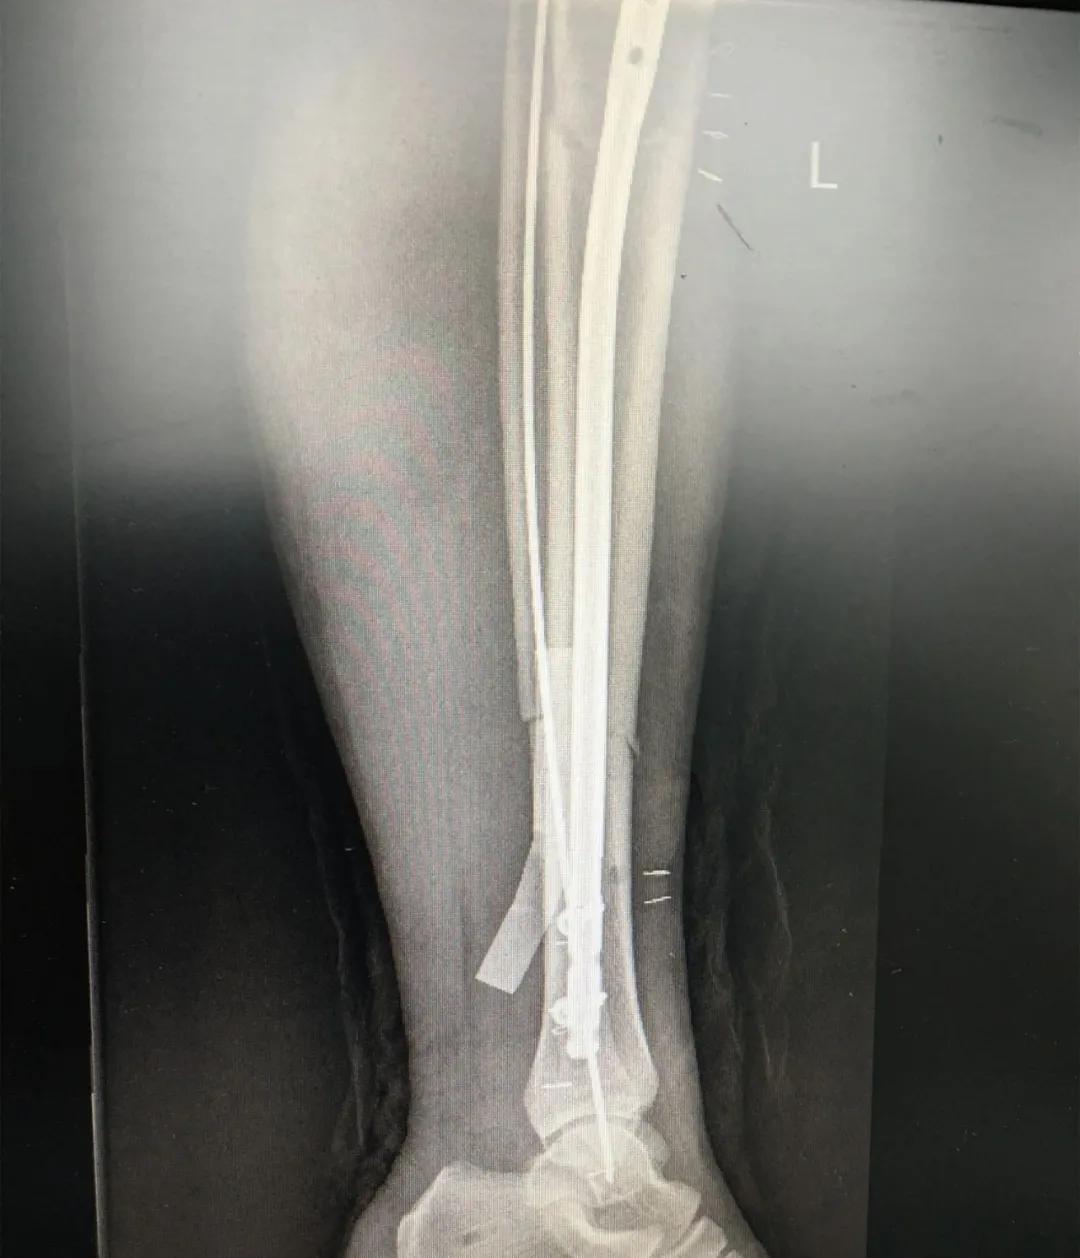

为患者实施的骨折微创复位固定技术是创伤骨科的特色技术。相较传统手术需要20公分的切口,微创手术只需要3公分左右。闭合复位髓内钉固定技术、经皮插板内固定技术(mippo技术)、闭合复位空心螺钉固定技术等一系列的微创复位固定技术,具有切口小、出血少、创伤小、愈合快、疤痕小等优点,骨折术后并发症明显降低,患者还可以早期负重功能锻炼。

另一位患者朱先生因车祸导致了右胫腓骨骨折,同样的小腿三段骨折,实施了微创闭合复位髓内钉固定术后,目前已经逐步进行康复功能锻炼。